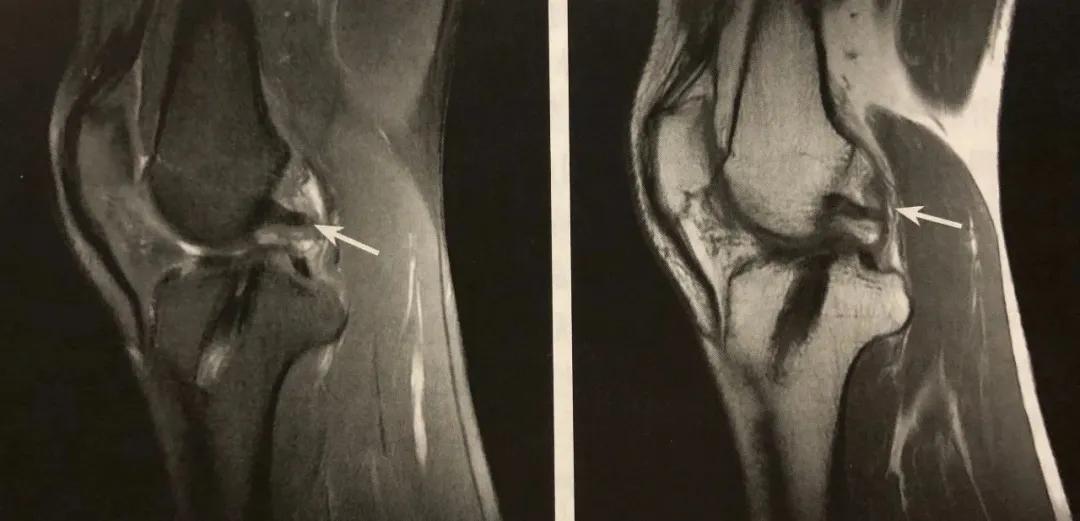

双后交叉韧带症

MRⅠ 矢状位像显示撕裂的半月板内缘碎片(箭头)与后交叉韧带形成“双后交叉韧带征”

在 MRI 膝关节近正中矢状位观察,正常的后交叉韧带前下方见到一条状低信号,较正常后交叉韧带小,走行与其近似平行,形似另一条后交叉韧带,称为双后交叉韧带征。部分病例 T2WI 可见灶样或线样高信号。

阅片要点:

1. 内侧半月板桶柄状撕裂间接征象;

2. 在 MRI 矢状位观察;

3. 典型表现为两条近似平行的弧形低信号带;

4. 后上方者为后交叉韧带,前下方者为撕裂的半月板内缘碎片;

5. MRI 诊断注意结合病史和排外相关变异。